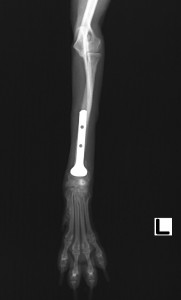

術後X線所見です。術後は安静を保ち、徐々に運動量を増やしていきます。本症例は骨癒合が順調に進みましたが、プレート下の骨にやや骨粗鬆が認められたため、段階的にインプラントの抜去を行ないました。

上画像は術後3ヵ月でスクリューを3本抜去した様子です。再骨折を防ぐため、一度に全てのインプラントを抜かず、段階的に抜いて行きます。